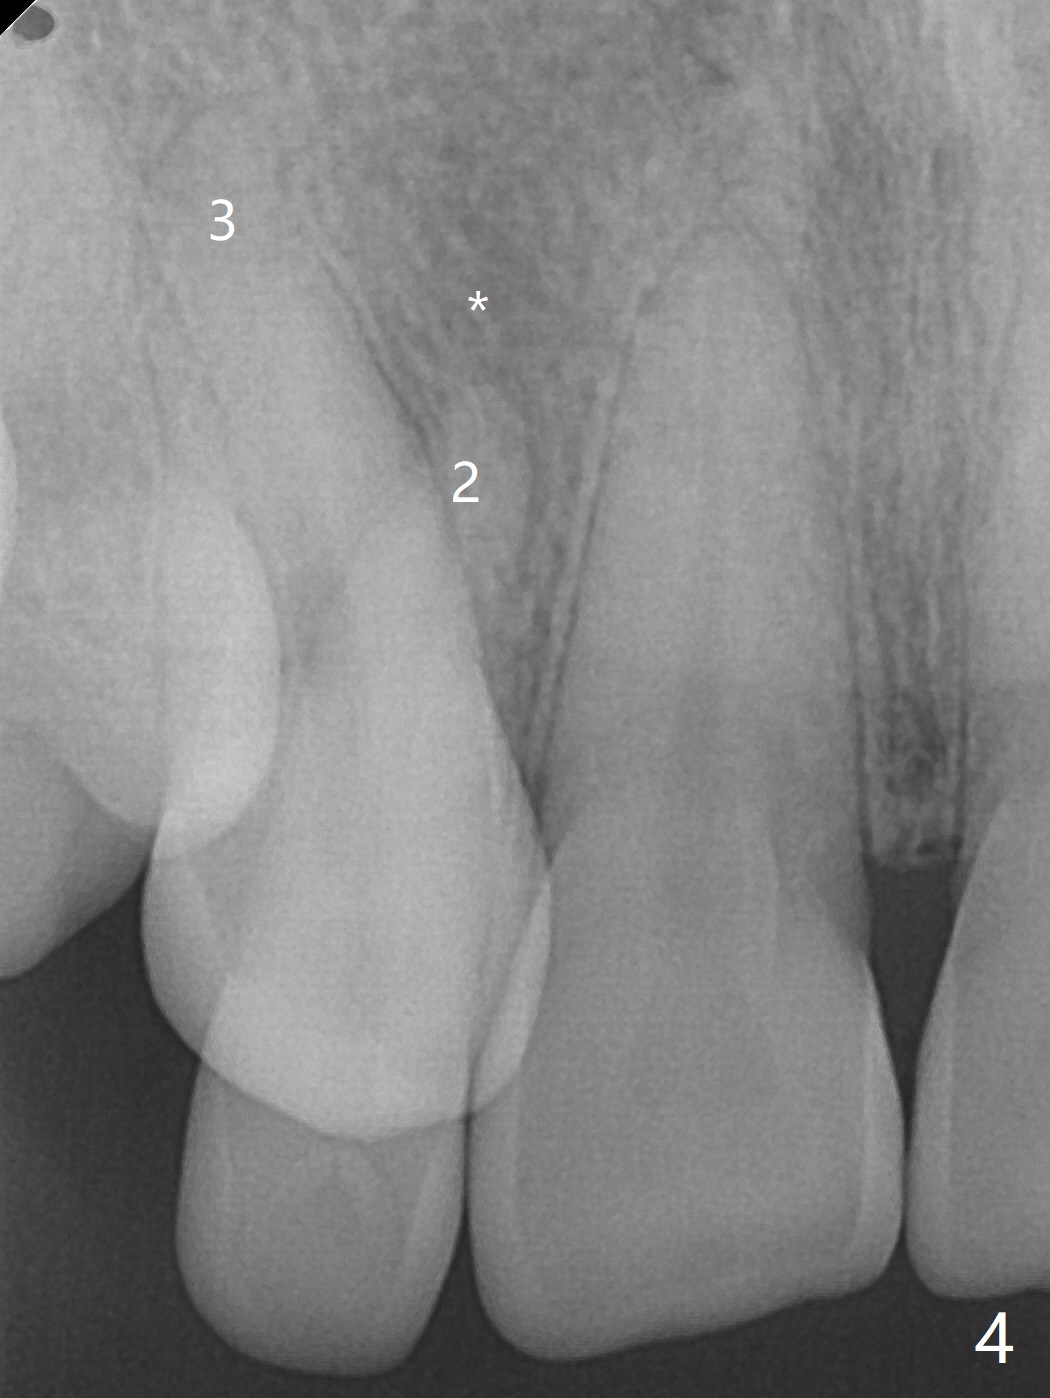

A 54-year-old woman seeks treatment for the tender upper right lateral incisor (Fig.1-4: 2 because of palatal cervical caries (Fig.3 <) and periapical radiolucency (*)), which overlaps with the palatal canine (3). One of treatment options is to extract the lateral and to orthodontically move the canine to the position of the lateral, particularly the root (Fig.5 arrow). When the lateral is removed, the labial bone of the canine is thin (Fig.6). Allograft is placed (Fig.8 * and dashed line), covered with Amnion-Chorion Allograft (Bioxclude) and sutured with 4-0 PGA (Fig.7). The wound heals 9 days postop (Fig.9,10). The patient is grateful because of no pain, which she thinks is due to bone graft, whereas Amnion-Chorion membrane is another contributory factor. The lateral root convexity remains 1 month postop (Fig.11 *); she is undecided upon orthodontic treatment.